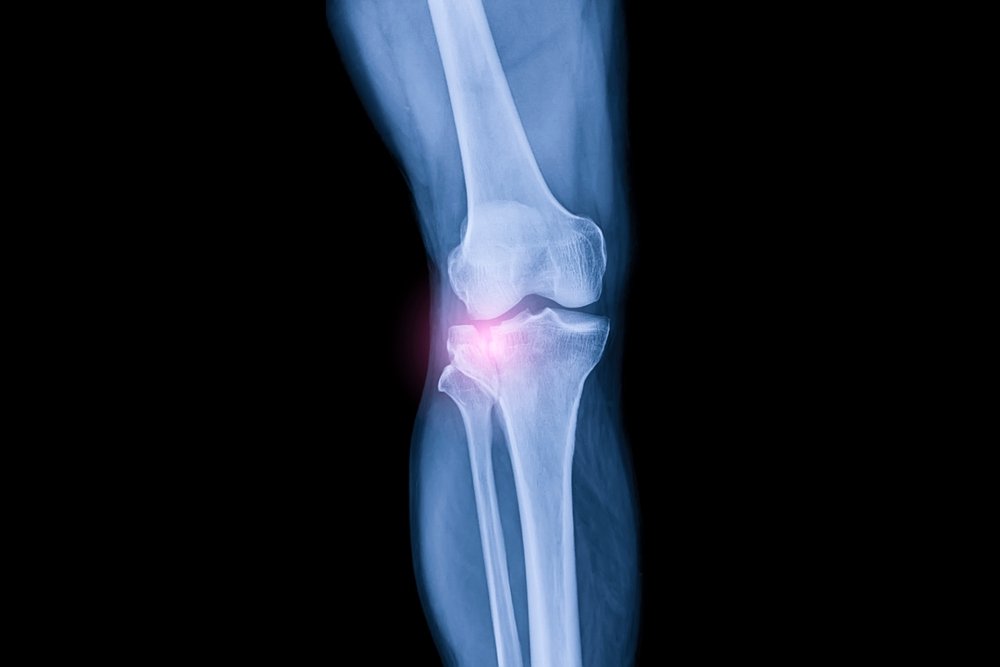

Что такое регенерация коленного хряща?

Регенерация коленного хряща — инновационная терапия, предназначенная для восстановления поврежденного хряща коленного сустава.

Это минимально инвазивное лечение включает в себя стимулирование роста новой хрящевой ткани и заживление дефектов суставного хряща, предоставляя пациентам альтернативу традиционным инвазивным хирургическим методам, таким как замена коленного сустава.

Устраняя повреждения хряща в таких областях, как подлежащая кость или поврежденный суставной хрящ, это лечение облегчает боль в суставах, поддерживает более здоровый рост хряща и улучшает долгосрочное здоровье суставов.